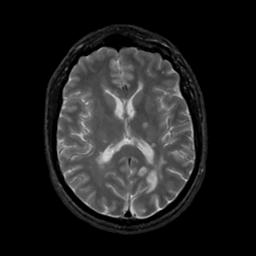

MR Study #3, February 24, 1991 -- Slice #28

[Home][Help][Clinical][Tour 1][Tour 2] Slice 28